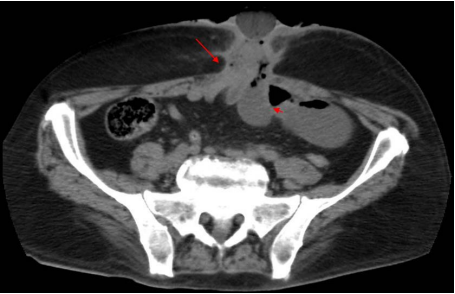

Foto 2: Corte axial de tomografía de abdomen contrastada con evidencia de fistula enterocutánea. (Flecha: indica la fistula entero-cutánea; Cabeza de Flecha; indica el conglomerado de asas intestinales

Por los hallazgos, se decidió realizar una laparotomía exploradora. Encontrando una fístula entero-cutánea y entero-entérica formada por un conglomerado de asas intestinales. Se encontraron 5 asas comunicadas entre ellas (Foto 3); el extremo proximal a 80cm del ángulo de Treitz y el extremo distal a 140 cm de la íleo-transverso anastomosis; se reconoce recaída tumoral en la fístula (anatomía patológica extemporánea: Adenocarcinoma). Se resecó el trayecto fistuloso en la pared abdominal y las asas intestinales involucradas (Foto 4).